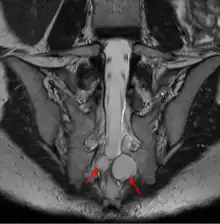

Un kyste de Tarlov (KT) ou kyste périneural, est une dilatation locale de l'espace sous-arachnoïdien se formant au contact d'une racine nerveuse, le plus souvent sacrée, dans la zone de transition entre arachnoïde et périnèvre (membrane externe du nerf). Il est fréquent et le plus souvent asymptomatique, mais peut parfois causer des symptômes neurologiques : on parle alors de maladie de Tarlov.

Le kyste de Tarlov est le plus souvent asymptomatique et découvert fortuitement lors du bilan d'imagerie d'une lombosciatique[5]. Cependant le kyste en lui-même peut être une cause de sciatique, voire lorsqu'il est situé au niveau sacré de troubles vésicosphinctériens (mictions impérieuses, dysesthésie anale...)[5]. Chez la femme, le kyste de Tarlov peut être la cause d'un syndrome d'excitation génitale persistante[6].